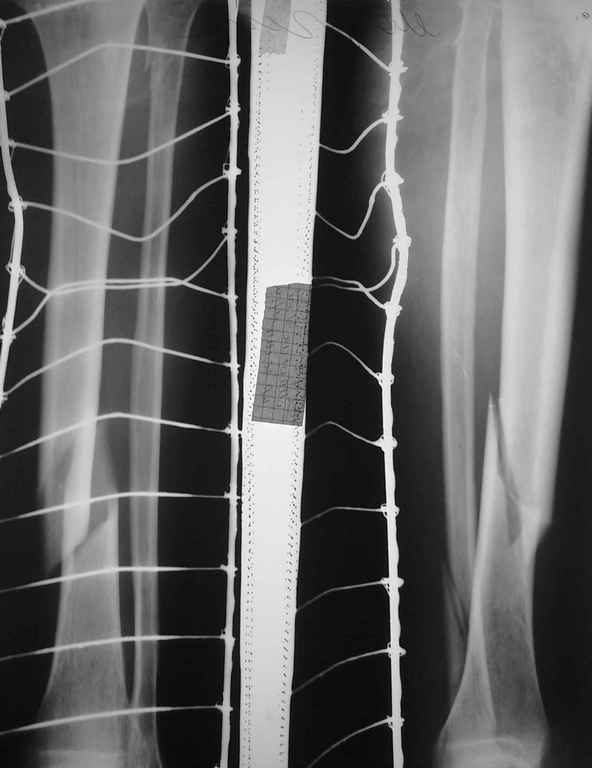

Здравствуйте уважаемые коллеги, поздравляю с Рождеством Христовым!Необходим Ваш совет относительно тактики лечения пациента В.50 лет с распространенным псориазом (болеет ок.20 лет) и данным видом перелома.

Предполагалось произвести БИОС, однако сопутствующая патология, по утверждению ряда коллег, является противопоказанием к оперативному лечению.Благодарю за участие.

делал доступы и через псориатические бляшки, осложнений не отмечал. Можно оперировать любой методикой какой вы владеете. Судя по фотографии, перелом носит открытый характер со средней зоной повреждения мягких тканей. Оптимальным, на мой взгляд, будет внеочаговый остеосинтез. Единственное, очень смущает вид мягких тканей, они жизнеспособны? Пульсация на стопе есть? Стопа живая???

Перелом закрытый,пульсация и чувствительность стопы не нарушены

Судя по состоянию мягких тканей перелом далеко не первой свежести. Думаю стоит привести в порядок мягкие ткани, а дальше исходить из возможностей. Я бы остановился на БИОС, несмотря на псориаз.

Добрый день! Сам страдаю псориазом более 10 лет. Может конечно не сообщу новость, но у псориатиков кожные повреждения заживают быстрее. А картина на снимке у вашего пациента, очень далека от ужасной. Оперируйте без вопросов, никакой особенности по именно инфекционным осложнениям притягивать не стоит. Михаил Васильев.

Добрый вечер!Я бы предпочел ВО ЧКО по Илизарову,стабильно-функциональный метод,на с/н/3 голени имеются трофические нарушения?Перелом вторично открытый?Меньше агрессии,чем БИОС и МОС.Удачи!